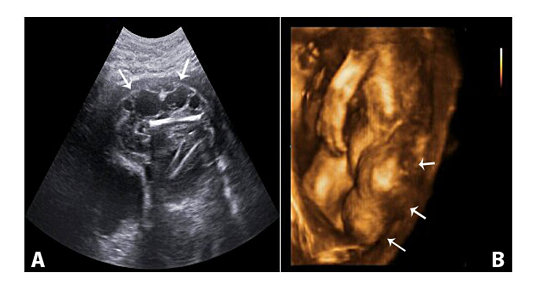

A 31-year-old woman, gravida 3, para 2, was first referred at 22+3 weeks for further evaluation of a cystic lesion in the fetal abdomen. Antenatal follow-up was uneventful until the fifth month of gestation, and the first trimester antenatal aneuploidy screening tests were normal. Her medical history was also normal. On referral, transabdominal sonography was performed by Medison SonoAce X8 system (Seoul, South Korea) and equipped with a 3DC2-5 volumetric probe. A singleton, live, female fetus with irregular subcutaneous cystic mass, measuring 55 × 38mm in size at the widest plane on the left inguinal region was revealed by ultrasound (Figure 1).

Fetal biometry was appropriate for the gestational age. This cystic mass was extending to the left leg until the knee. Color Doppler flow mapping revealed no blood flow within the lesion. The possible diagnosis was fetal inguinal lymphatic malformation. The assessment of amniotic fluid and placenta were normal.

The distinctive imaging feature of the lymphatic malformation is the absence of blood flow, which is observed with the use of color Doppler ultrasonography to distinguish it from hemangioma.5 In this case, the fetal MRI also provided more information about the infiltration of the lesion to the fetal thoracal structures, and complemented the role of sonography. Traditionally, ultrasonography has been used as the primary screening method for prenatal diagnosis. MRI may provide information about both the anatomy and the extension of the lesion, thus providing the information essential for parental counselling.3 Also, 3D ultrasound helped to identify the lesion clearly and completely, and make the consultation with pediatric surgeons and parents more comprehensive.2